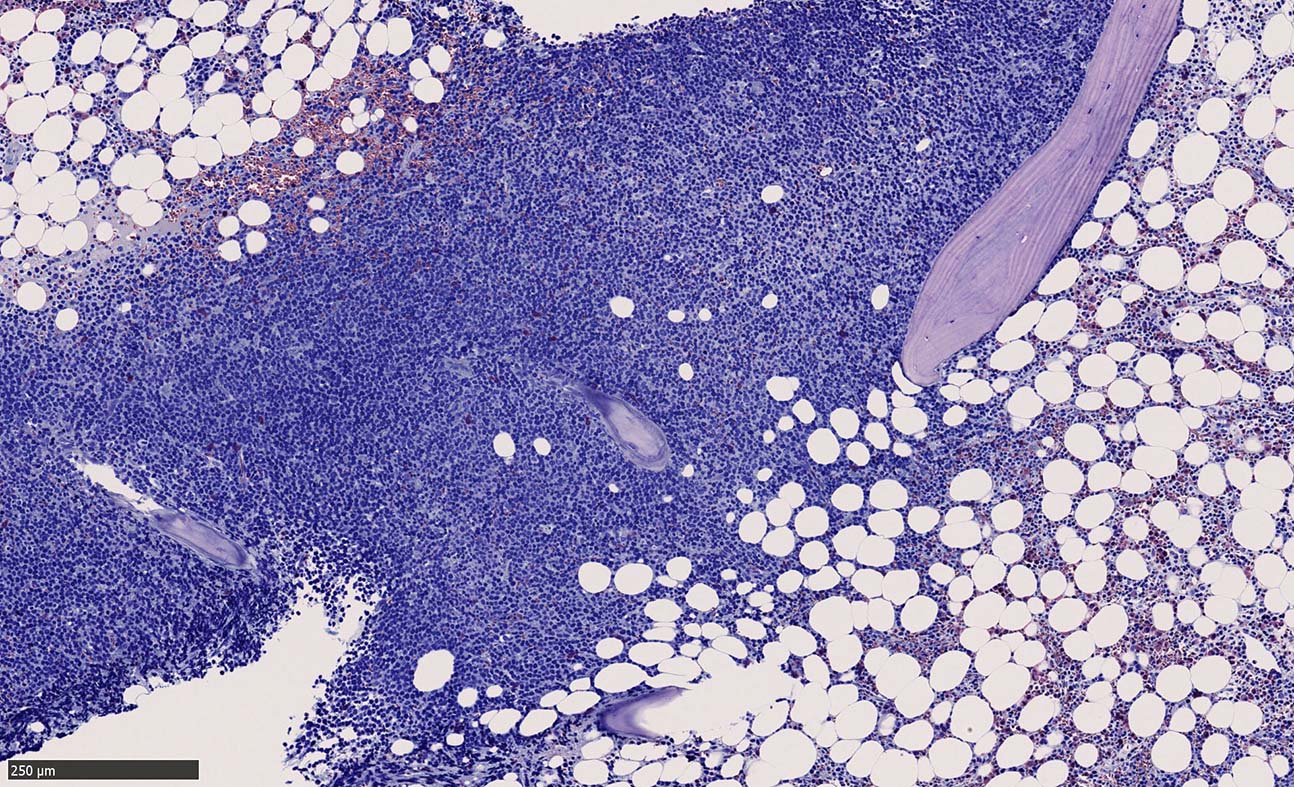

Bone marrow involvement of mantle cell lymphomaの症例

骨髄骨梁間に密なASD-Giemsa陰性の小型~中型円形細胞の浸潤が認められる.

MCLは60-90%の症例で骨髄に浸潤する. *1*2*3*4*5. 骨髄浸潤の最も一般的なパターンは, focal random(限局性, ランダム)で, 80%以上の症例でみられる.

骨梁間(interstitial)には約50%, びまん性浸潤は20~30%の症例でみられる。*1,*6 とくに, 傍骨梁浸潤は45%の症例に認められる. 時には、濾胞性リンパ腫に似た傍骨梁のみの浸潤を認めることもある. まれに、顕著な類同内浸潤を伴う症例も報告されている。*7